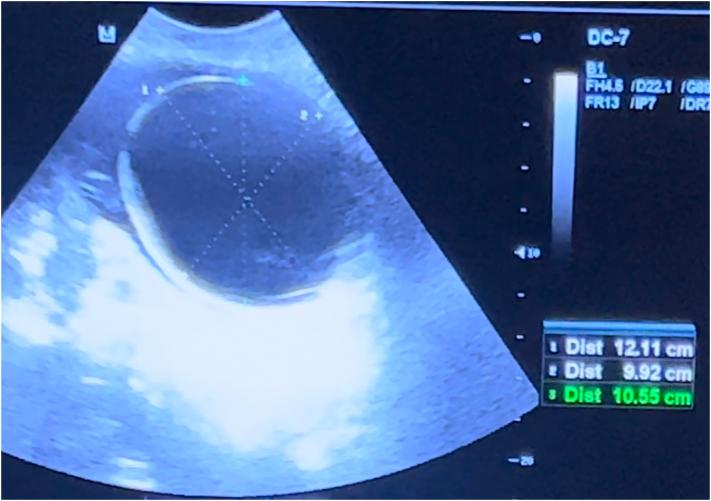

A 14-year-old adelocant girl with primary amenorrhea and severe persistent pelvic pain presented to the gynecology outpatient clinic in our hospital. On pelvic examination, there did not see cervical external os. Radiologic imaging revealed a markedly both fluid intrauterine cavity and upper vaginal canal. The patient underwent general anesthesia, a partial incision of the septum was performed. At discharged time sponge soaked with estrogen cream and 22 number catheter were placed in her vagina to prevent stenosis.

一名14岁原发性闭经且伴有严重持续性盆腔疼痛的青春期女孩到我院妇科门诊就诊。盆腔检查时未见到宫颈外口。影像学检查显示子宫腔和阴道上段均有明显积液。患者接受全身麻醉,进行了横隔部分切开术。出院时,在其阴道内放置浸有雌激素乳膏的海绵和22号导管以预防狭窄。